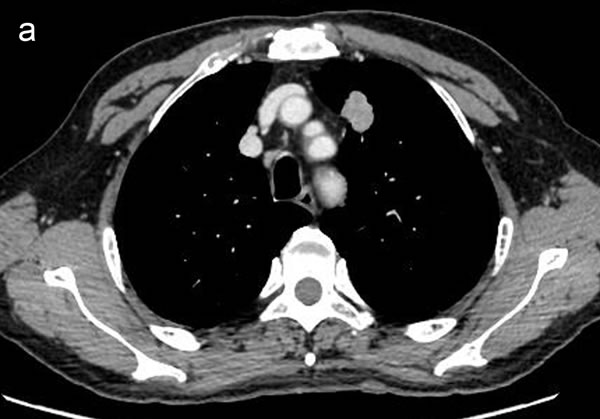

Figure 2: Representative CT images showing homogeneous enhancement (a) and heterogeneous enhancement (b).

CT image analysis and post-processing

Two radiologists (with 6, and 3 years’ experience in thoracic CT imaging, respectively), who were blinded to clinical and histiopathological data, reviewed all CT images separately. They were asked to identify pulmonary lesions and to evaluate the enhancement heterogeneity according to the following criteria: homogeneous enhancement was defined as more than 90% of the tumor area was occupied by the same CT attenuation as ascertained by visual assessment; otherwise heterogeneous enhancement was considered (Figure 2). In case of disagreement, the third reviewer with 27 years of clinical experience in thoracic imaging, made the final decision. Then, semiautomatic tumor segmentation was done in consensus by three radiologists using a designated multi-platform, free and open source software package for visualization and medical image computing (3D slicer, version 4.4.0; available at: http://slicer.org/) (Figure 3). Totally, 54 features were extracted and they were divided into four categories (Supplementary Table 1, Image features metrics are available at: https://www.slicer.org/wiki/Documentation/Nightly/Modules/HeterogeneityCAD), including (1) First-Order Statistics, (2) Morphology and Shape, (3) Texture: GLCM, and (4) Texture: GLRL.